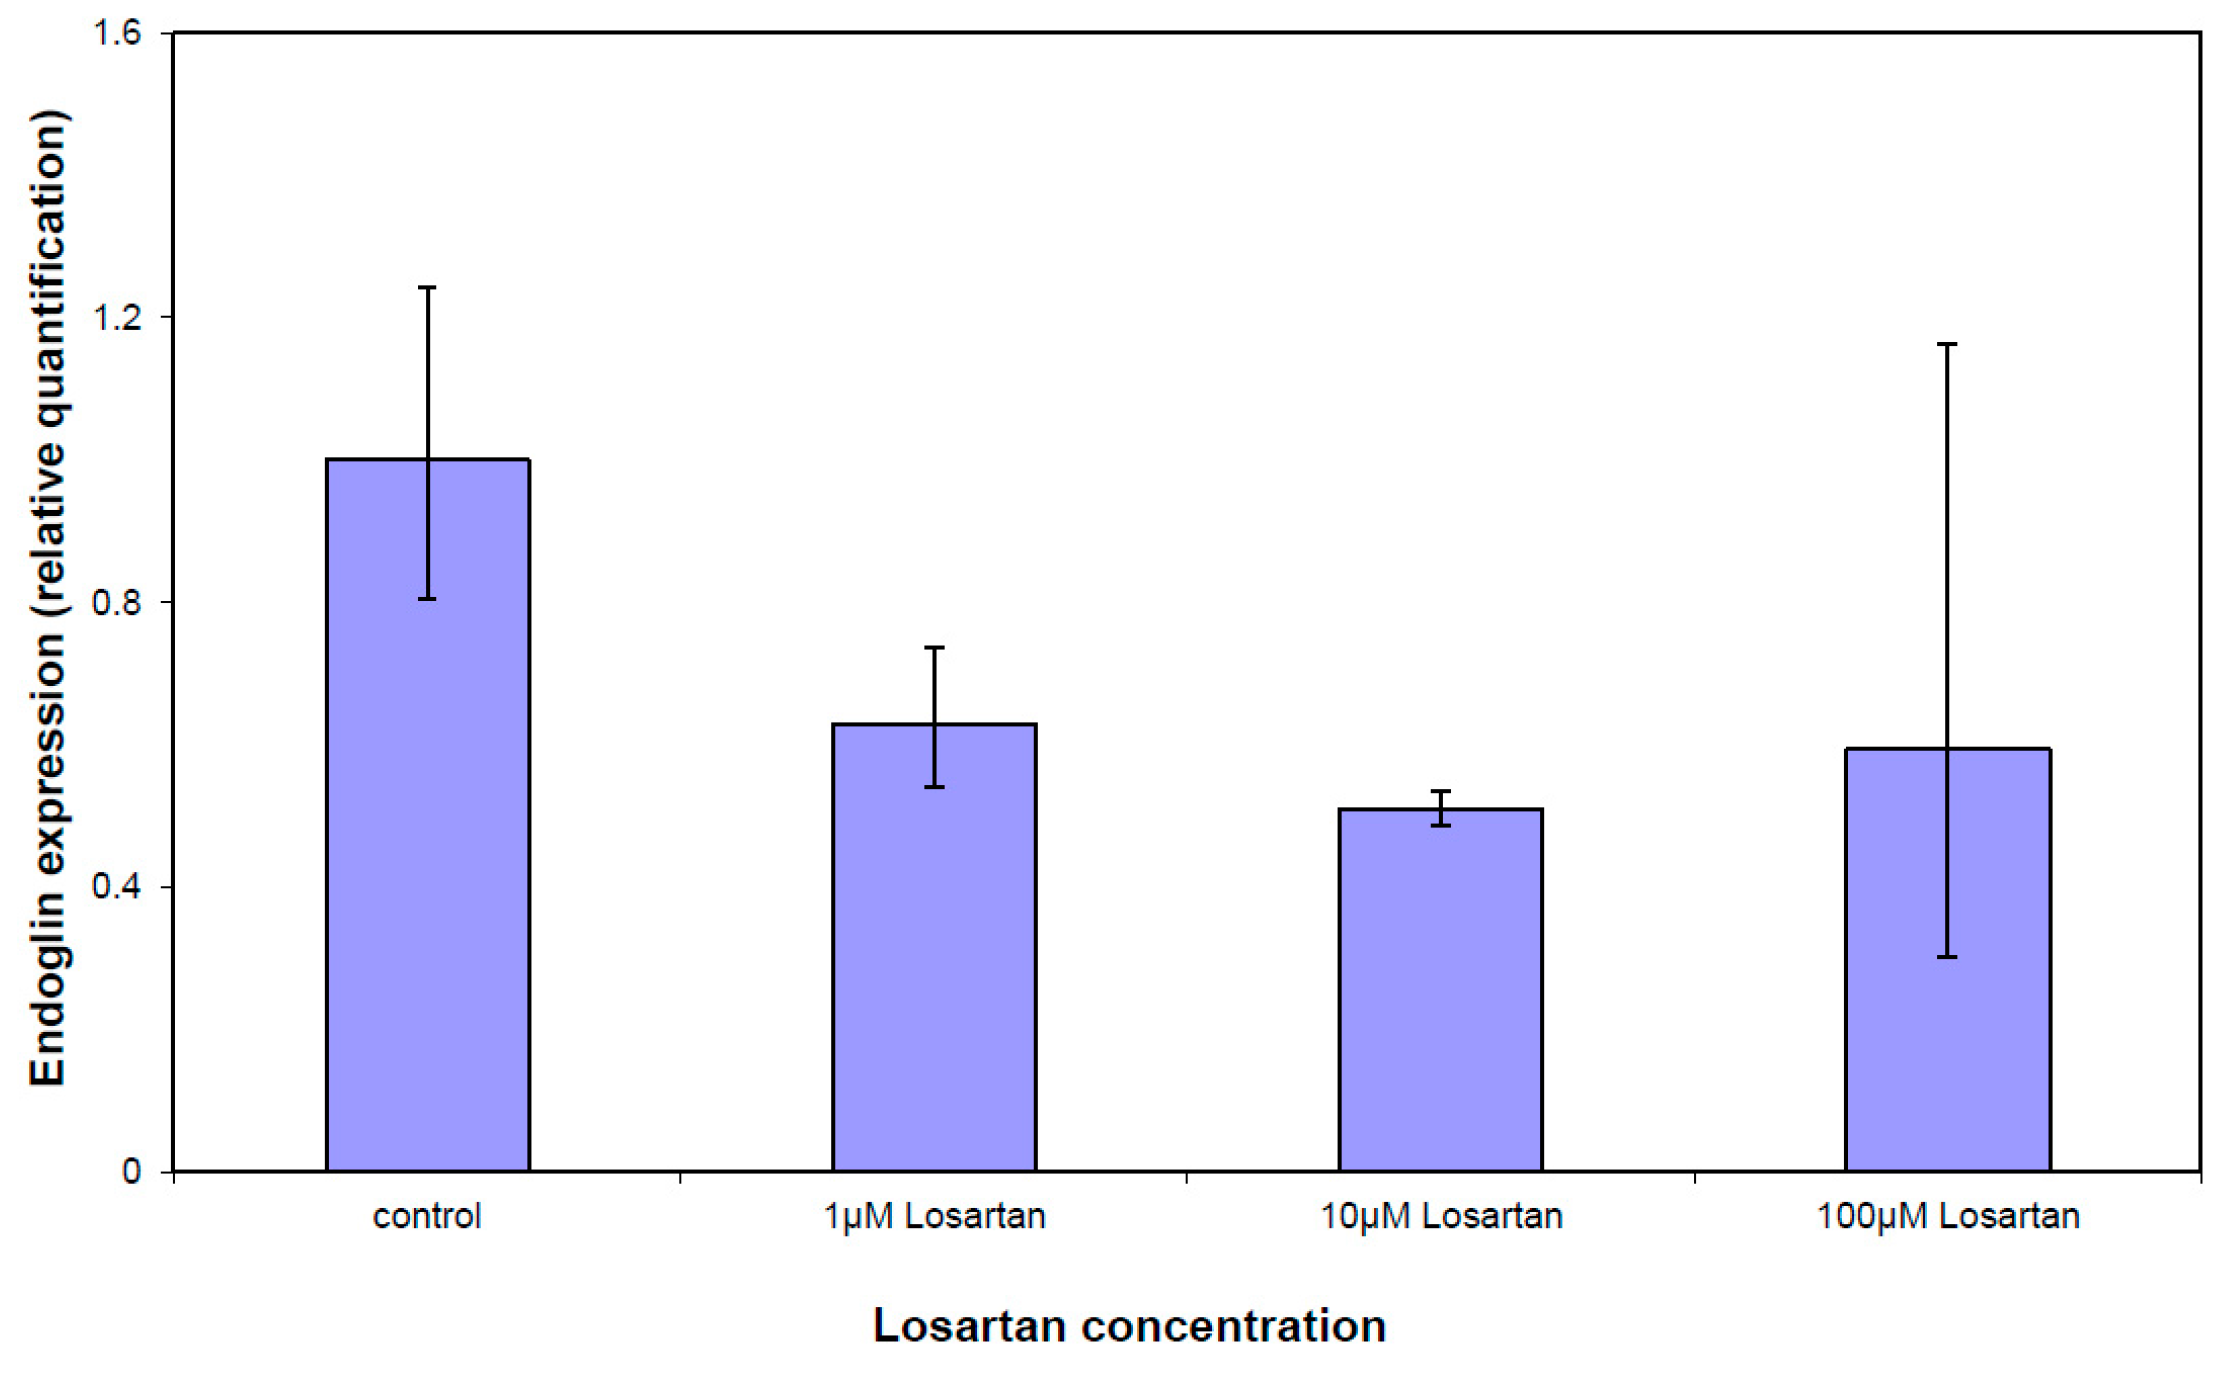

3.5. Gene Expression Analysis of the TGFβ Pathway

4. Discussion